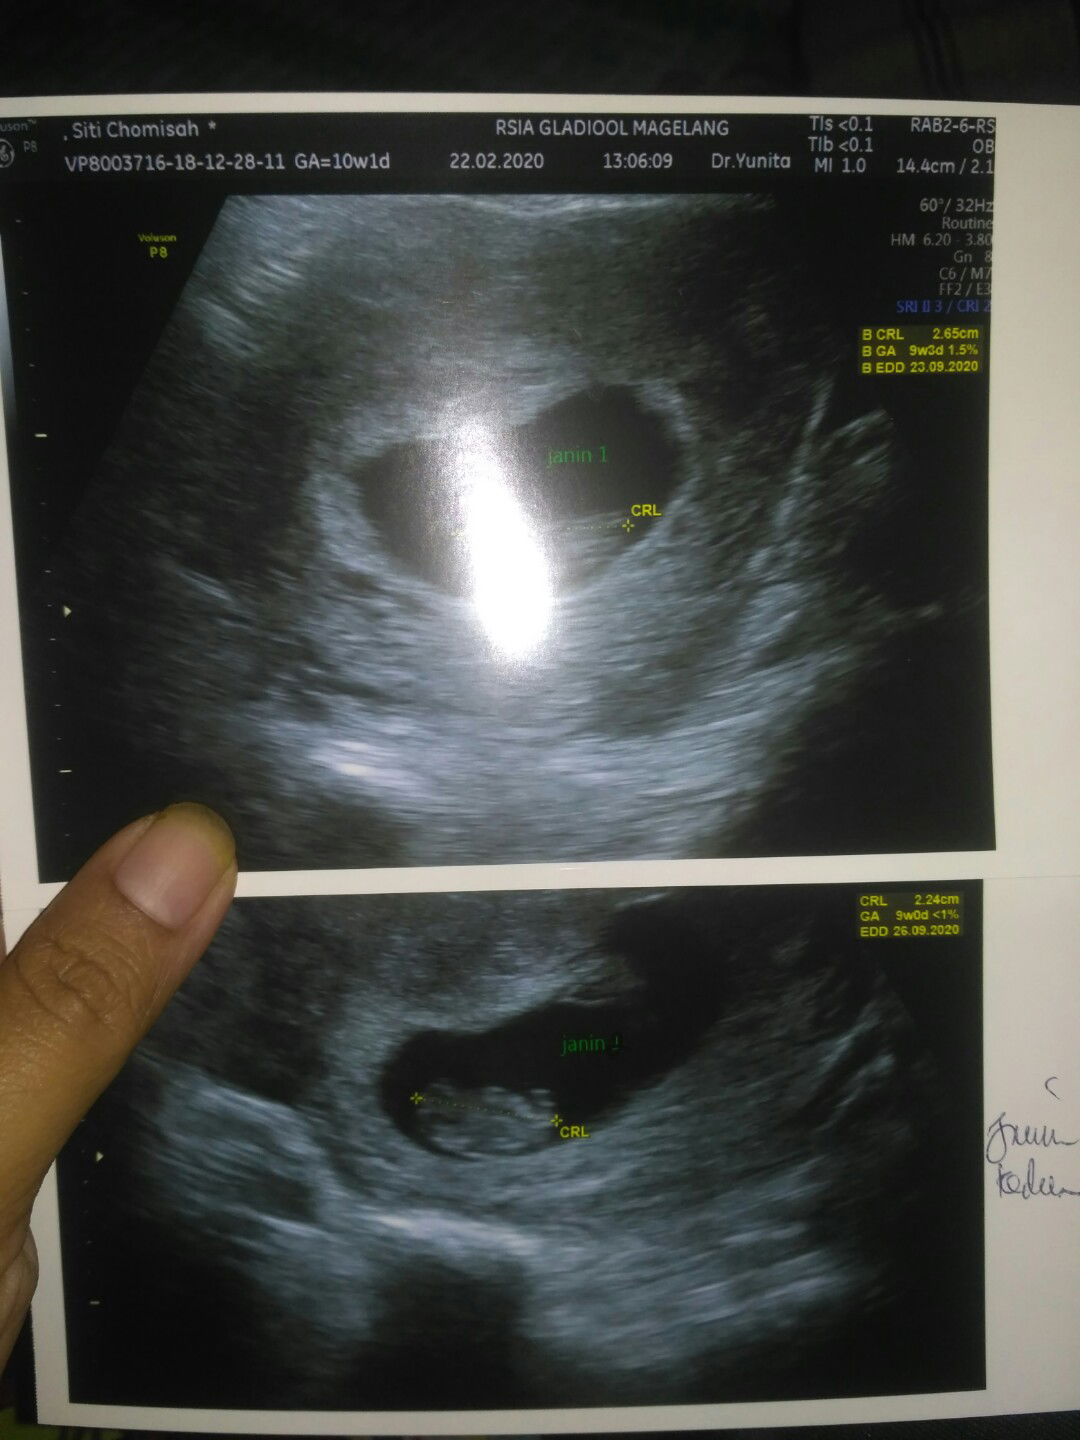

hamil kembar 2 kantong dan 2 plasenta